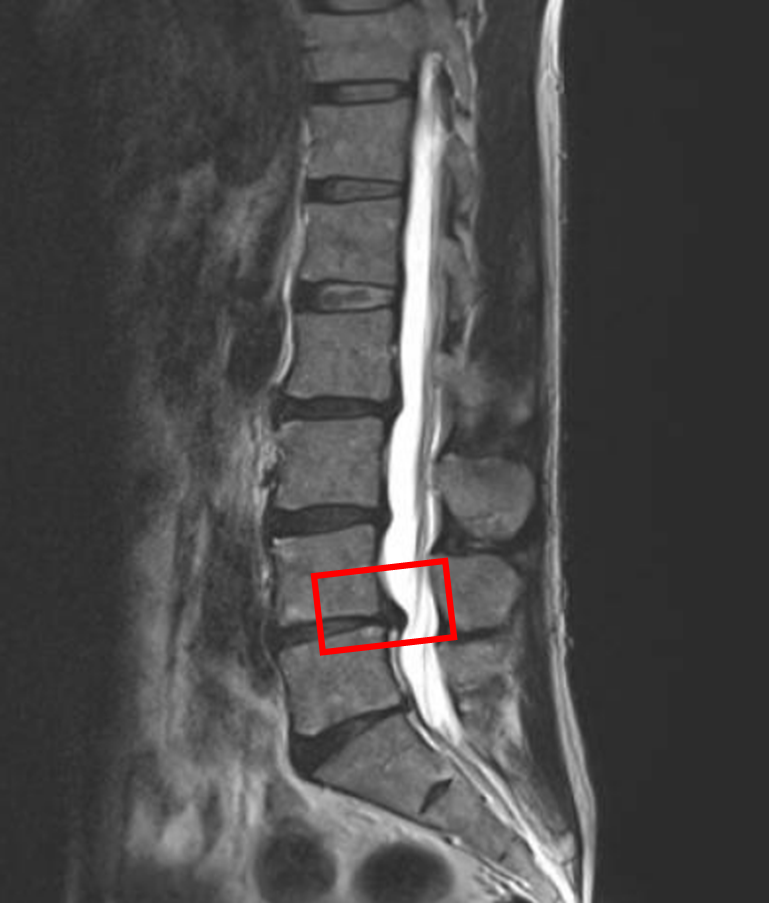

この患者様は赤い枠で示されている箇所(L4/5)にを椎間板ヘルニアを認めます。